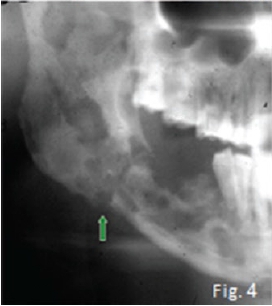

The cropped pantomograph (Fig 2) shows a "blurred/ fussy" appearance of the trabeculae due to loss of density. Signs of cortical destruction are also present. A provisional diagnosis of acute osteomyelitis was made which was confirmed histologically. Osteomyelitis is an inflammation of bone cortex and marrow that develops in the jaw usually after a chronic infection: No detectable radiographic features of the infection are discernible in the first 8-10 days (radiological principle: 30-60% decalcification before any changes are observed). About three weeks after the start of the infection irregular radiolucencies with enlargement of trabecular spaces are noticed (Fig 3). In the chronic stages, extensive areas of the bone may be destroyed and sequestra are formed showing the classic moth-eaten appearance and occasionally a pathological fracture may also be present (Fig. 4). Note the sequestration of bone in the anterior mandible on the coronal CT scan (Fig. 5) of another patient with chronic suppurative osteomyelitis The coronal T2 W. MRI scan (Fig. 6) shows the sequestrated bone (no signal black) is surrounded by zones of high signal intensity (white signal) representing the regions of active inflammation. Most cases of osteomyelitis of the jaw result from odontogenic infections, infections from a fracture site; or, rarely, haematogenous spread from a distant site, which is more common in the long bones. The cause of infection is most frequently Staphylococcus aureus, but haemolytic streptococci and Bacteroides are also encountered. The mandible is by far the most frequently affected; the adult maxilla is very seldom the site of osteomyelitis. The acute phase of suppurative osteomyelitis is sudden in onset and rapid in course. The patient experiences severe pain, fever, regional lymphadenopathy, and leucocytosis. Teeth in the region become loose and tender to percussion. When the mandible is involved there may be paraesthesia of the lower lip on the affected side. As soon as drainage is established, the pain eases, the temperature drops, the patient becomes more comfortable. Without treatment the infection may progress into a protracted chronic suppurative osteomyelitis. Differential diagnoses include malignancies and oteoradionecrosis.